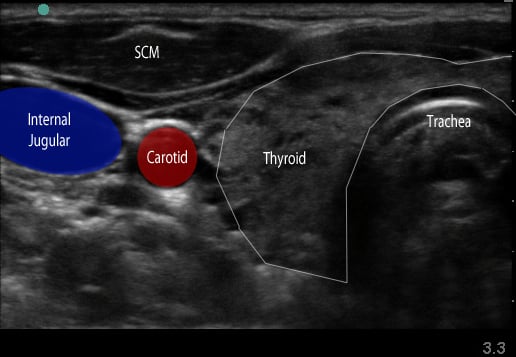

Figure 1. Transverse view over the sternocleidomastoid

- Use a high-frequency 8-12 MHz linear probe and begin scanning transversely over the anterior neck at the level of the cricoid. (Figure 1)

- Probe indicator oriented to operator’s left.

- Depth should be set between 4-8 cm, depending on the size of the patient’s neck.

- Trachea should be clearly seen as a midline hyperechoic arc.

- Slide the probe laterally to the lateral border of the sternocleidomastoid (SCM) (Figure 1), which is a thin muscle superficial to the carotid and jugular.

- Move the probe inferiorly to identify the anterior scalene muscle deep to the lateral border of the SCM. (Figure 2)

- Triangular muscle that is thicker caudally

- Lateral to the internal jugular vein

- If not apparent, slide the probe in a cranio-caudal direction along the lateral border of the SCM to find it

- Identify the middle scalene muscle posterior to the anterior scalene muscle.

- The interscalene space is between these 2 scalene muscles and contains the brachial plexus

- Visualize the brachial plexus here as a stack of circles with hypoechoic centers